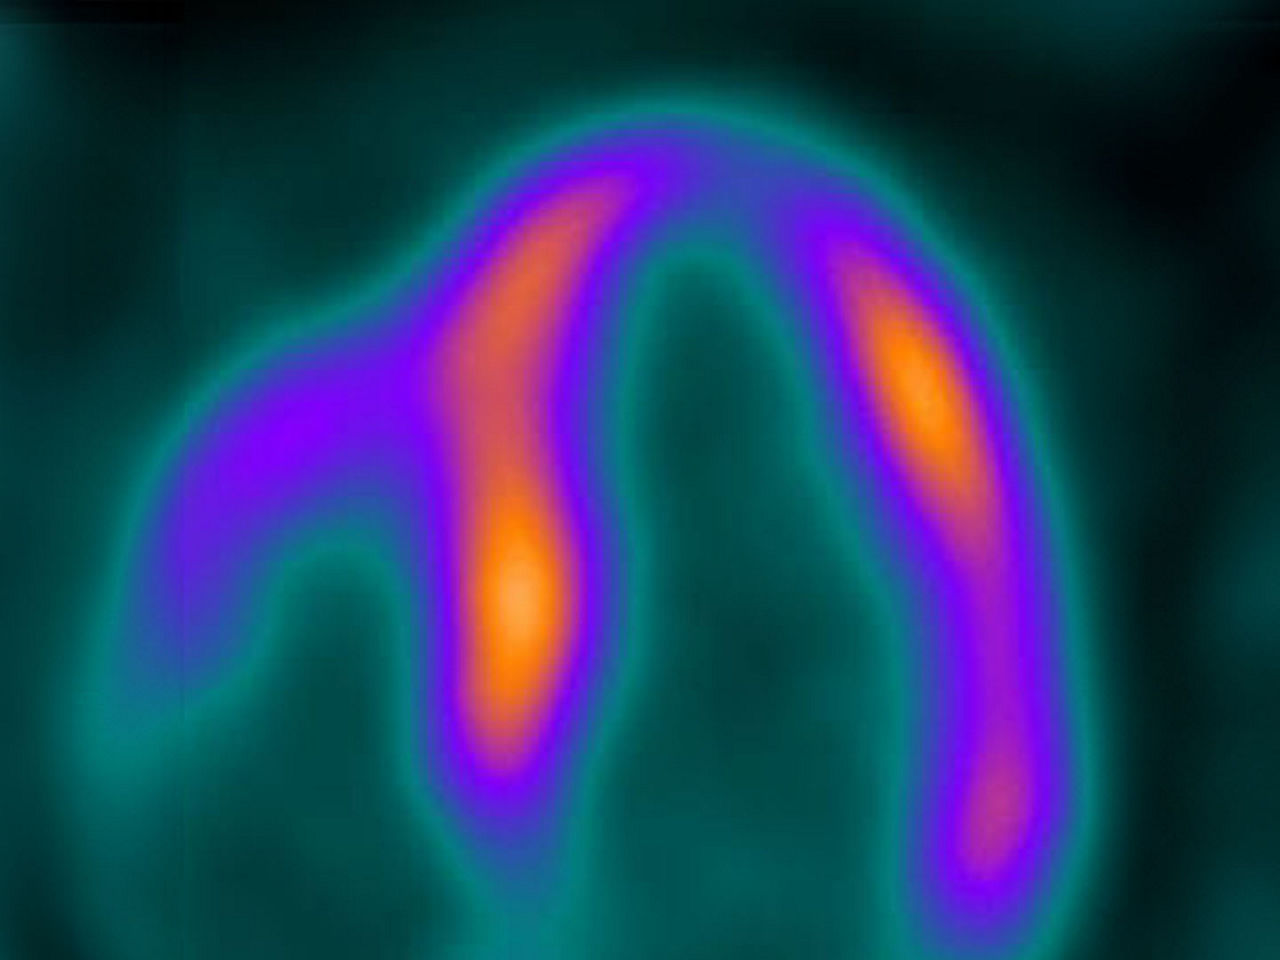

Seen here is a theranostics 18F-PSMA case, after prostate removal. There was suspected recurrence due to elevated markers. No pathological findings at the surgery area.

This image is a theranostics 68Ga-PSMA case for prostate cancer assessment response to treatment. There were pathological findings in the lymph nodes in the pelvic area.

Omni Legend is built with innovative capabilities to make it an industry-leading PET/CT platform, enabling exemplary diagnostic confidence for your team now and in the future. We designed Omni Legend with theranostics in mind by utilizing ultra-high sensitivity, high resolution, Q.Clear and MotionFree to help personalize dose as well as imaging 68Ga for diagnosis, staging or restaging. The first-of-its-kind Omni Digital Detector and Precision DL are designed to reach new levels of sensitivity and detectability for incredibly clear images. And the brand-new Omni platform gives you exceptional control over the future of your PET/CT capability going forward.